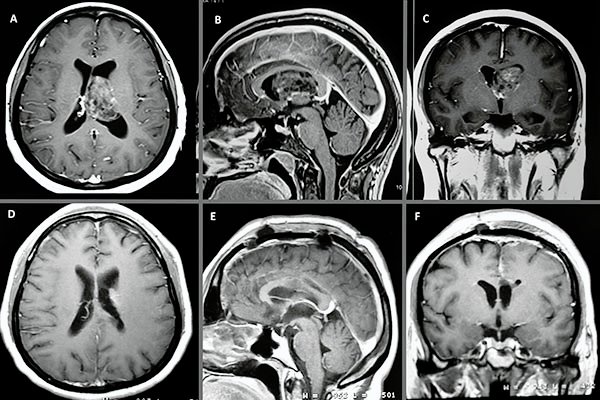

En la RM de encéfalo control, realizada 20 días luego de la cirugía, se observa huella de callosotomía anterior sin lesión focal intraventricular residual aparente (fig. 4).

Figura 4: A, B y C) Cortes axial, sagital y coronal pre quirúrgicos ponderados en T1 con contraste. D, E y F) Cortes axial, sagital y coronal post quirúrgicos ponderados en T1 con contraste.